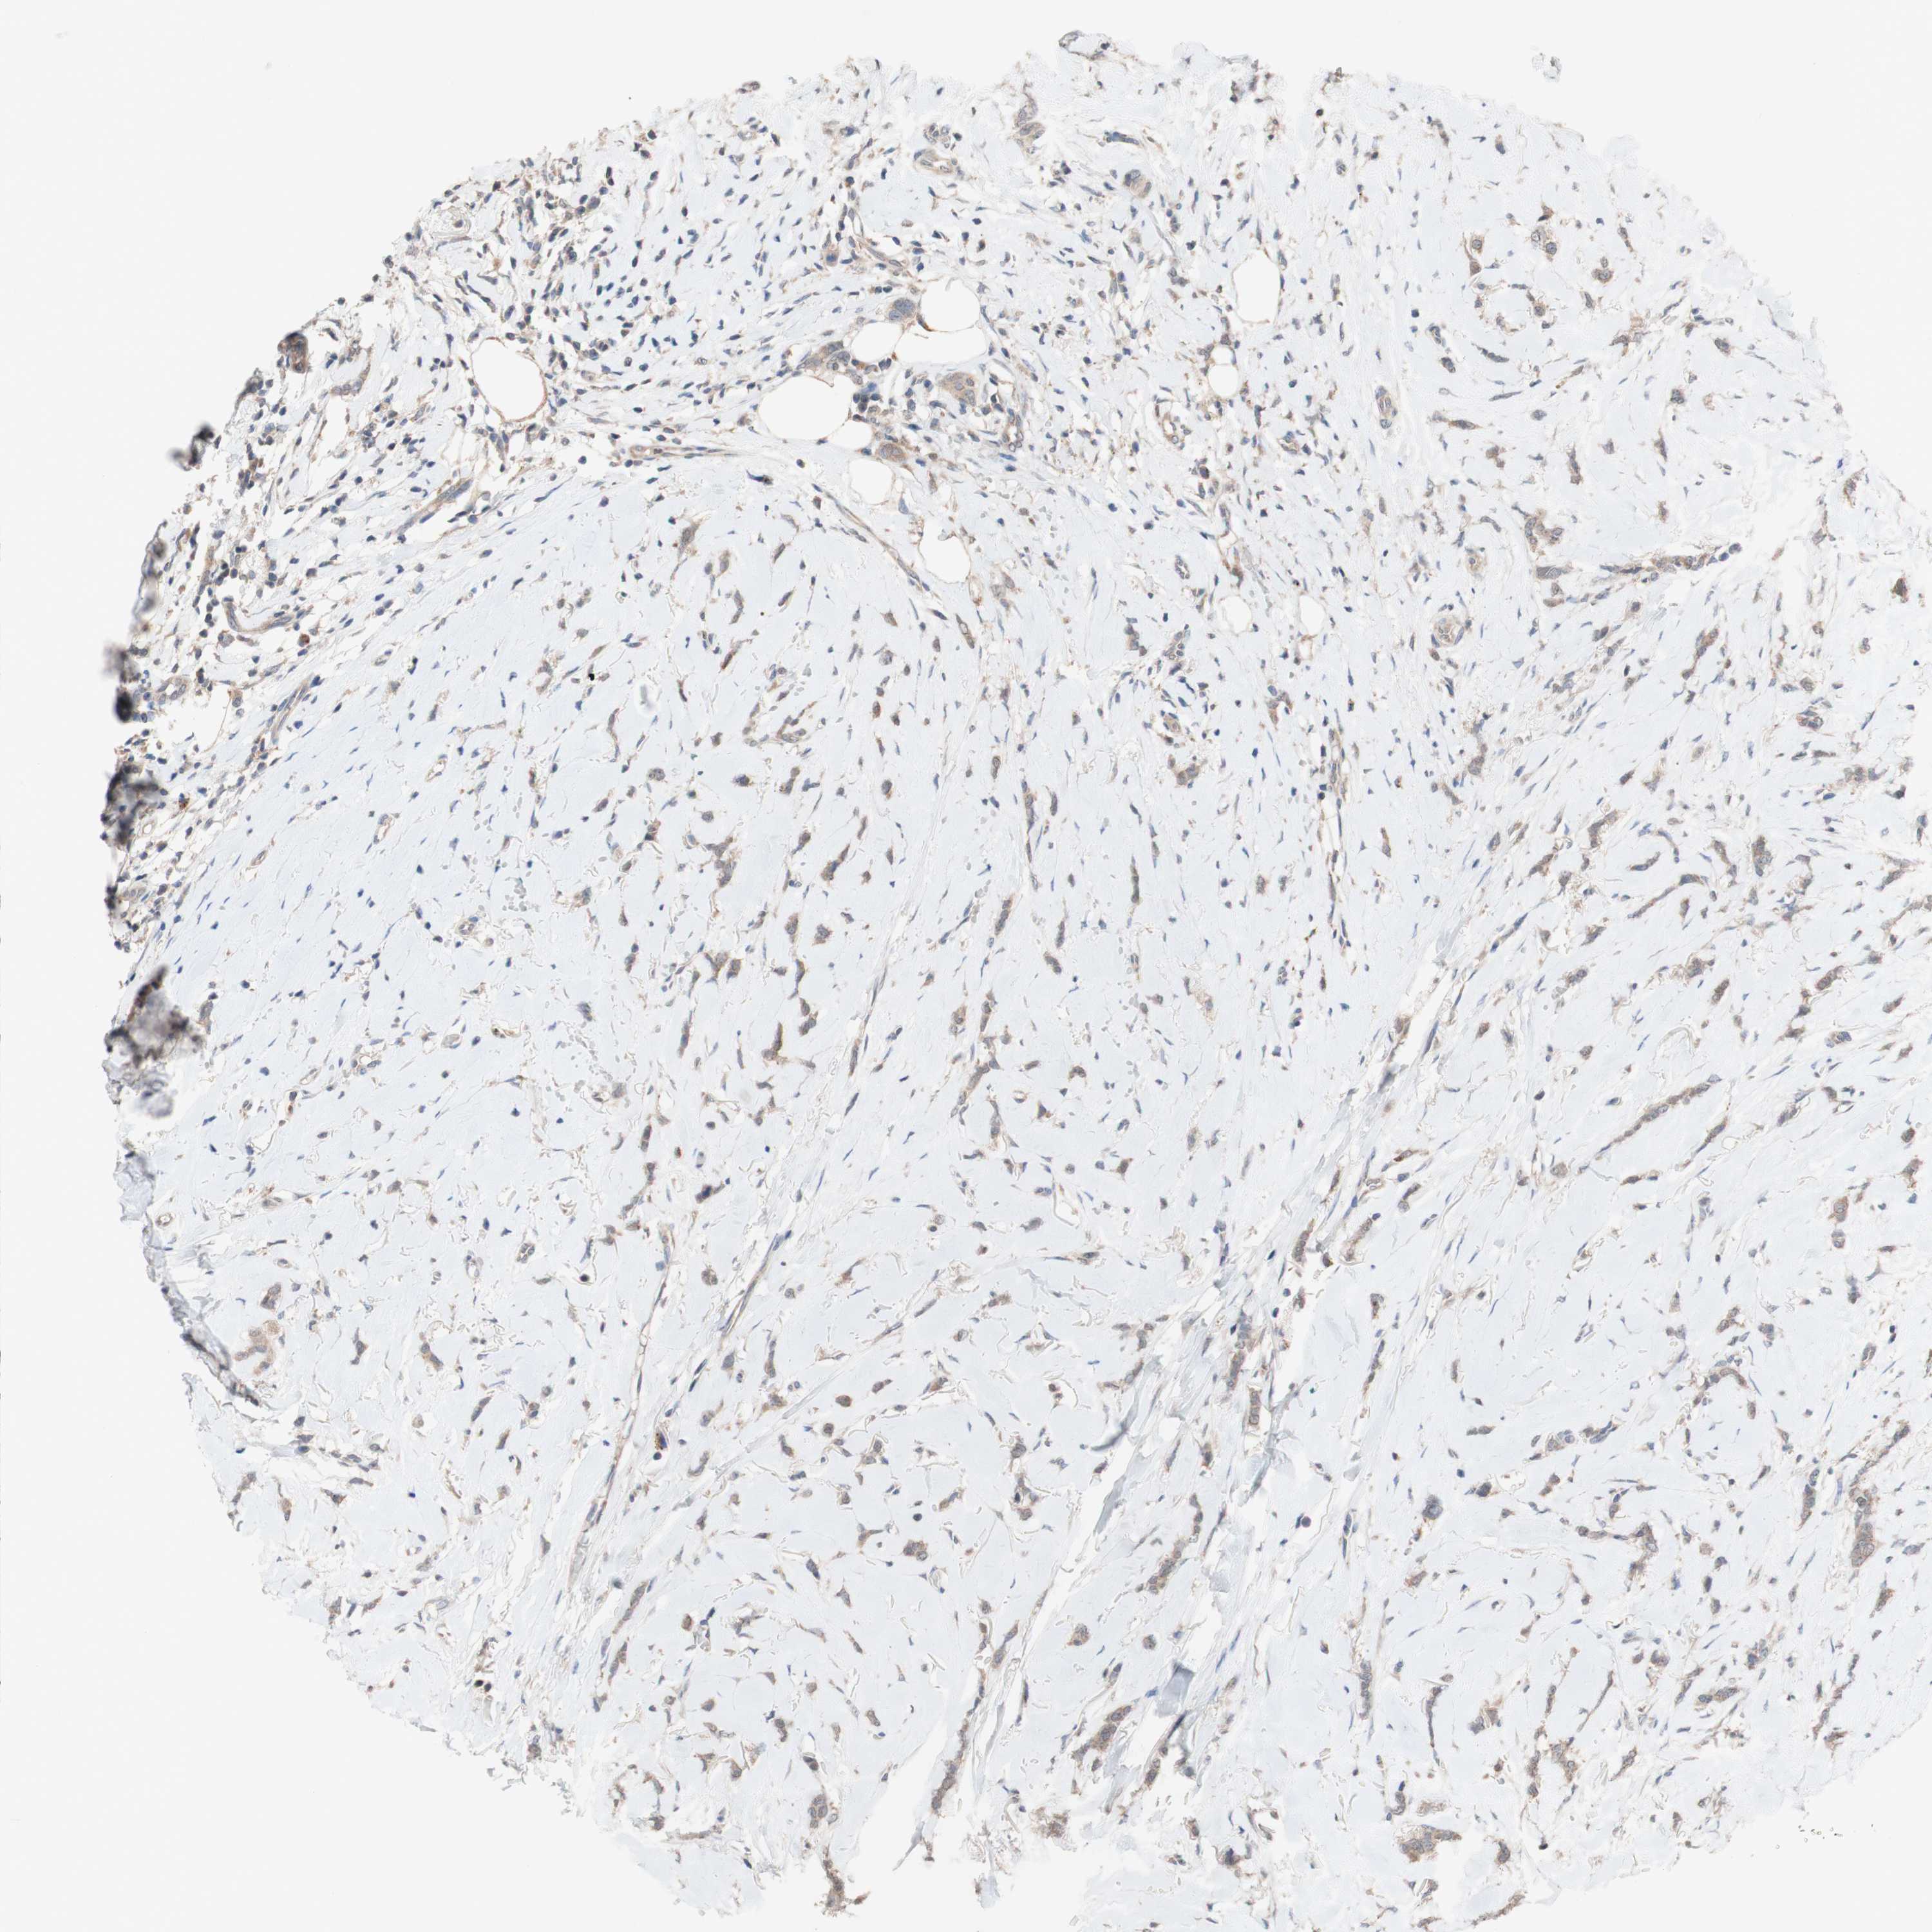

CANCER BREAST CANCER Show tissue menu

BRCA TCGA BRCA VALIDATION PROTEIN EXPRESSION